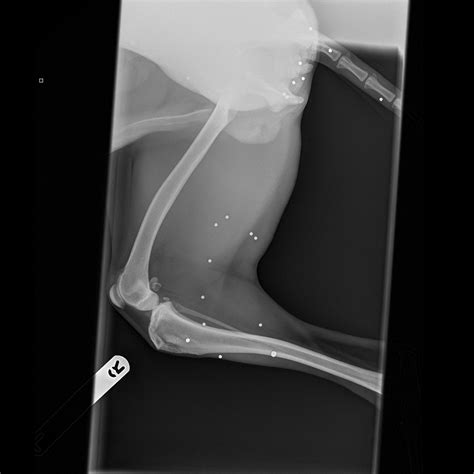

• X-Rays or Imaging: Imaging tests may be ordered to assess the extent of internal damage, especially if the BB is still lodged in the body.